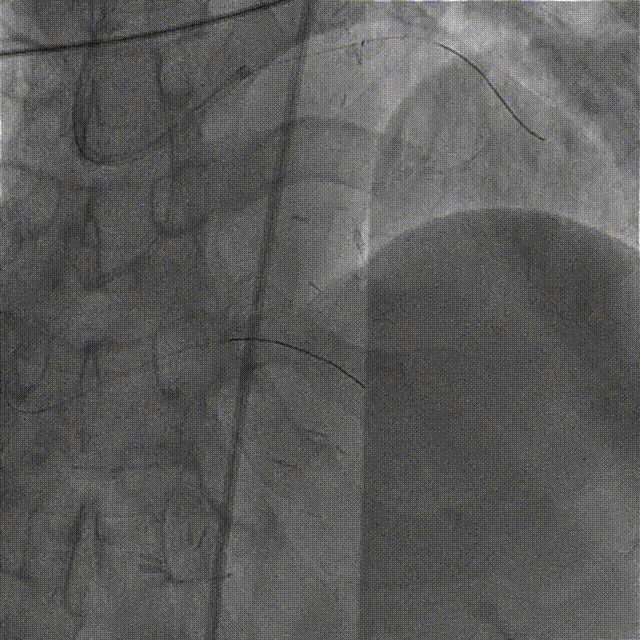

于LAD病变处由远及近依次植入XIENCE Alpine 2.5mm x 18mm和XIENCE Alpine 3.0mm x 23mm支架各一枚。

造影示支架定位良好,D1开口受压90%狭窄,交换一根SION导丝穿支架网眼至D1远段,用Pinoeer1.5mm x 15mm、Pinoeer 2.0mm x 15mm球囊至D1开口处扩张。

FOXTROT NC 2.5mm x 15mm、FOXTROT 3.0 mm x 15mm后扩球囊后扩球囊至支架内后扩,以实现支架的充分贴壁,并对LAD远段进行球囊扩张,造影显示TIMI血流III级。

术后行IVUS检查示:支架定位贴壁扩张良好,LAD开口MSA:7.43mm2。